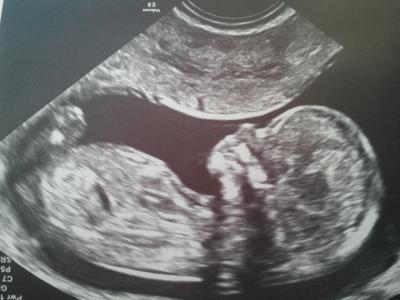

Hallo Mädels, erst einmal gaaaaaanz lieben Dank, dass Ihr Alle so lieb an mich gedacht habt. Die NFM war wundervoll und die Ärztin hat auch ganz lange geschallt. Die Nackenfalte ist zurückgegangen und auch die sonstigen Organe , Nasenbein etc. war wunderbar entwickelt. Die Ärztin ist also voller Hoffnung, dass das ein gesundes Baby wird. Trotzdem habe ich mich dann für die Chorionzottenbiopsie entschieden, weil ich eben sicher sein möchte. Sie war nicht unbedingt angenehm und ich hatte danach auch Schmerzen. Jetzt geht es aber wieder und die Ärztin hat ja ne Stunde nach der Punktion noch mal geschallt. Also mit dem Zwerg ist alles okay. Am Montag bekomme ich dann das Ergebnis, allerdings erst Nachmittag. Ich bin schon ziemlich positiv eingestellt , aber will ja doch noch das Ergebnis abwarten. Ich freu mich also erst einmal ganz vorsichtig und drück Euch alle nochmal für Euer Daumendrücken........ Hab Euch lieb !!!!!!!!!!!!!!!! Achja.....mein Zwerg ist jetzt 6,8 cm groß und mit Beinchen ja noch meeeeehr :D :D :D Seid ganz lieb gedrückt Mandy

Bild zu Bin zurück mit Foto im Gepäck ;) - Forum für August - Mamis